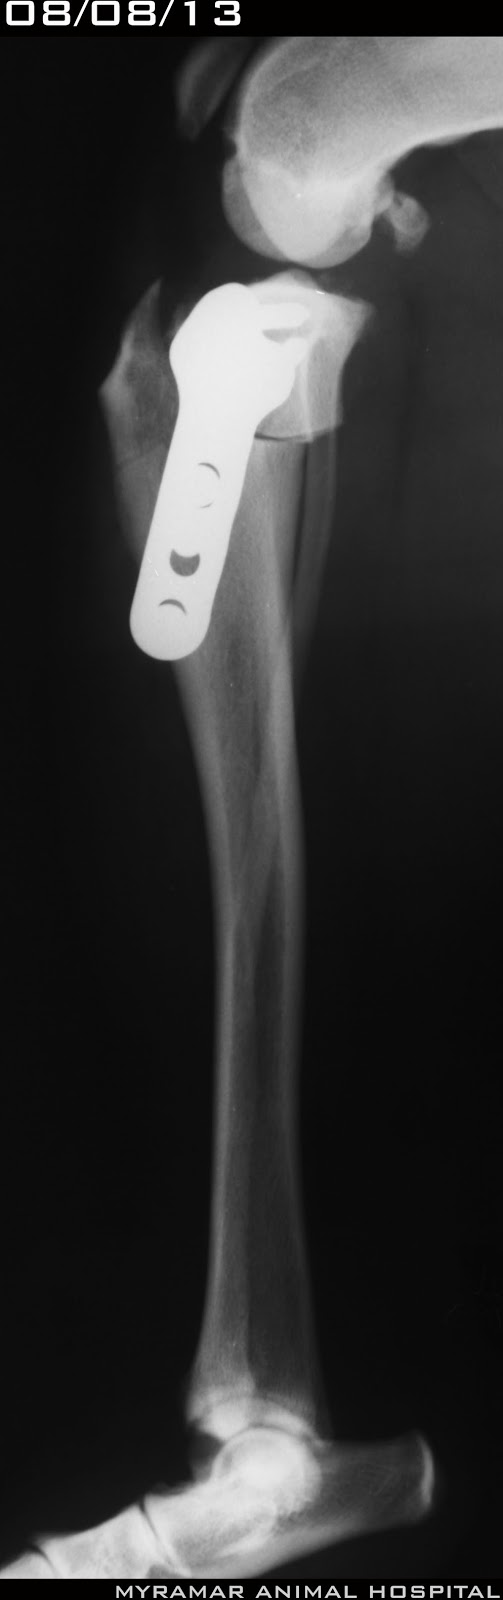

Oscar, italian bolognese de 6 años y 10.9 kg, llega referido al hospital con rotura de ligamento cruzado craneal.

Tras estudio radiológico se determina un avance de la tuberosidad tibial de 4.5mm

Se adelanta quirúrgicamente la tuberosidad tibial utilizando cuña de titanio poroso de 4.5x11x13mm y cerclaje de 0.6mm

Se presentan radiografías pre y postquirúrgicas del caso